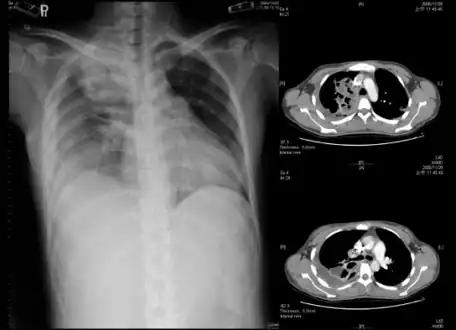

Lungs

Empyema